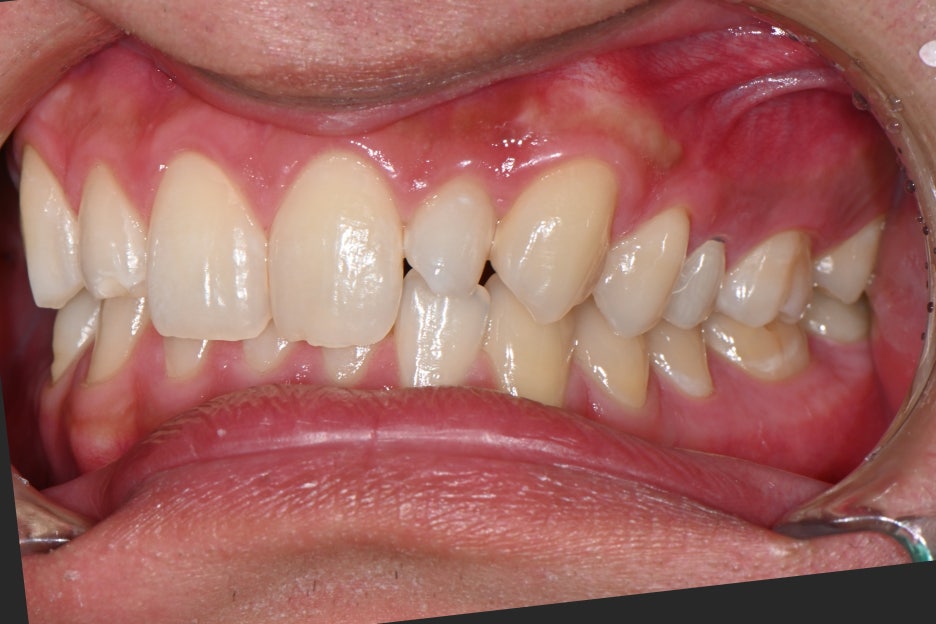

특히 양쪽 앞니 옆에 위치한 작은 치아가

선천적으로 작아 보이는 형태였고,

색도 맞지 않아 전체적으로 웃을 때

인상이 흐려지는 상태였습니다.

1.앞니 옆 치아가 작게 나 있는 형태

사람마다 치아 크기와 형태는 다르지만,

양쪽 균형이 크게 다르면 밝기를 높여도

자연스러움이 나오기 어렵습니다.